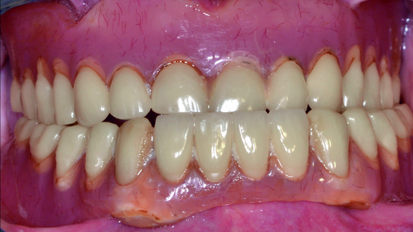

The main problem that brings patients to our surgery is an edentulous maxilla, which motivates the patient to want a functional restoration, with particular...